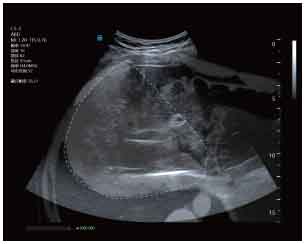

CT-Ultrasound real-time fusion

3D navigation and tracking

CT-Ultrasound Fusion in PCNL